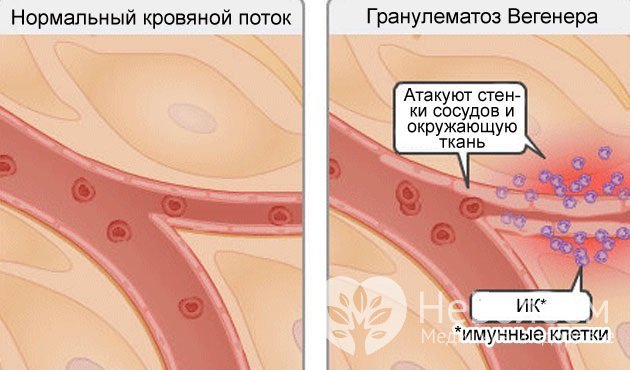

Гранулематоз Вегенера – аутоиммунное гранулематозное воспаление стенок сосудов (васкулит)

Гранулематоз Вегенера – аутоиммунное гранулематозное воспаление стенок сосудов (васкулит)Причины и факторы риска

Точные причины возникновения гранулематоза Вегенера неизвестны. Учитывая, что в крови при рассматриваемом заболевании обнаруживаются иммунные комплексы, его относят к аутоиммунным патологиям. Предположительно, болезнь развивается в результате ошибки иммунной системы, вследствие которой ткани сосудистых стенок воспринимаются иммунной системой как чужеродные и подлежат разрушению. К этому могут привести различные воспалительные процессы, в том числе инфекционные.

При гранулематозе Вегенера иммунные клетки атакуют стенки сосудов и окружающую ткань

При гранулематозе Вегенера иммунные клетки атакуют стенки сосудов и окружающую тканьИммунная система, определяя собственную ткань как чужеродную, вырабатывает к ней антитела. Антитела повреждают стенки кровеносных сосудов, что влечет образование участков воспаления, то есть гранулем. Постепенно увеличиваясь в размере, гранулемы закрывают просвет сосуда. В итоге нарушаются кровоснабжение тканей, процессы тканевого дыхания и метаболизма.